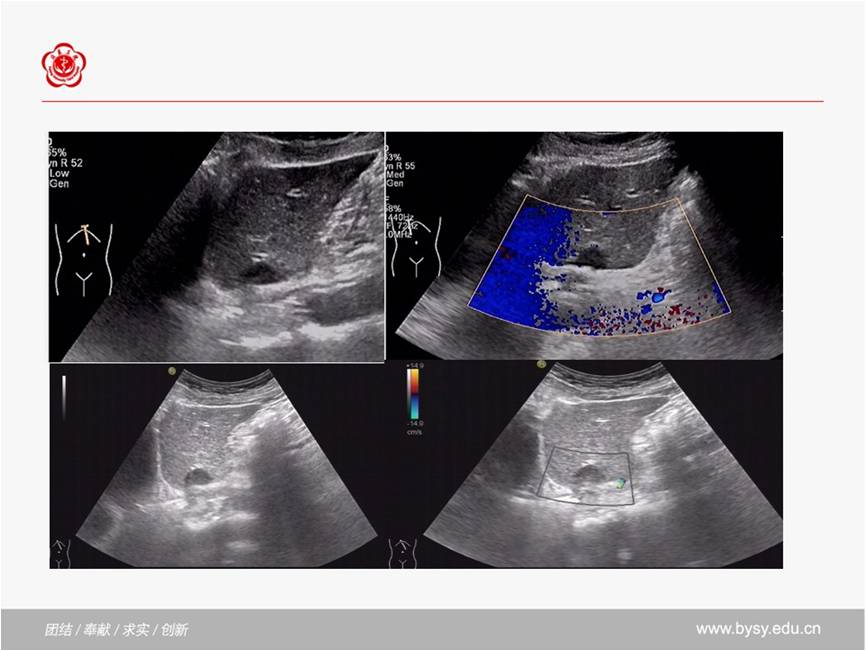

肝脏占位性病变之肝腺瘤